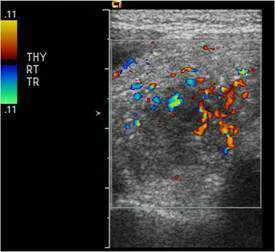

⼀位女性病患右側甲 狀腺及右下邊脖⼦淋巴腺無痛性腫⼤,其右側甲狀腺灰階及彩⾊杜⼘勒超⾳波檢查如圖,最可能的診斷 為何?

本題考慮一位女性病患出現右側甲狀腺及右下頸部淋巴結無痛性腫大,提供右側甲狀腺的灰階(B-mode)及彩色杜卜勒(color Doppler)超音波影像,要求判斷最可能的診斷。無痛性甲狀腺腫塊合併頸部淋巴結腫大,配合超音波影像特徵,是甲狀腺乳突狀癌(papillary thyroid carcinoma, PTC)的典型臨床表現。

本題共提供三張超音波影像(THY RT TR/SAG 標示,即右側甲狀腺横切及縱切面):

影像一(B-mode 橫切面):

- 右側甲狀腺內可見一低回音性(hypoechoic)實性結節,邊緣不規則、界線不清晰。

- 結節內可見多發性點狀強回音(punctate hyperechoic foci),即微鈣化(microcalcifications),對應病理上的砂粒體(psammoma bodies),此為甲狀腺乳突狀癌最具特異性的超音波特徵。

- 結節後方無明顯聲影增強(posterior acoustic enhancement),與囊性病灶不同,支持實性惡性病灶。

- 右側甲狀腺整體體積略增大,內部回音不均勻。